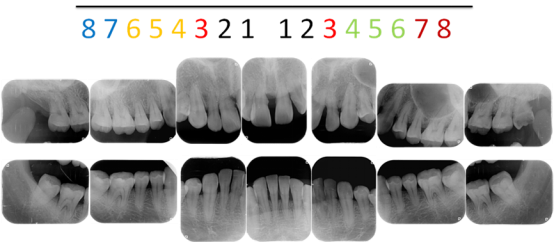

全口根尖片

1.为什么要拍牙片?

牙片是治疗牙齿过程中重要的手段之一,在治疗前可以用于发现病变程度;治疗中确定治疗范围和深度;治疗后用于观察疗效。通过牙片,口腔医生可以了解蛀牙范围有多大,牙痛是由牙髓神经发炎、根尖炎症还是牙周炎等引起的,镶牙的条件是否足够,种植牙需要的骨量,发现发育畸形以及某些肿瘤等。另外,牙片还为医患沟通提供了很好的依据。